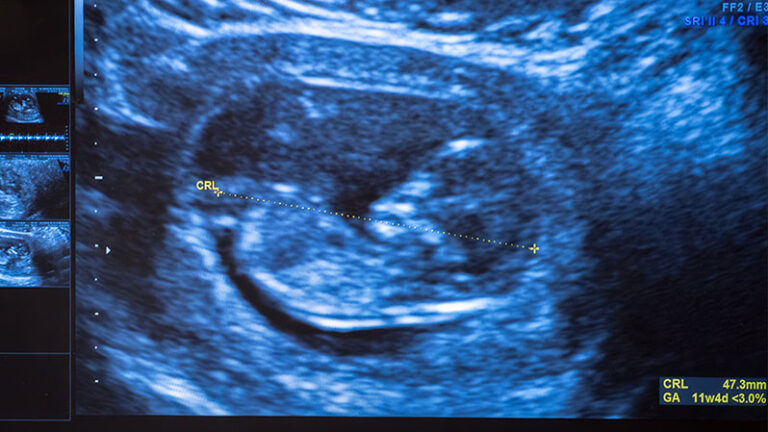

The Division of Maternal Fetal Medicine provides consultative care to pregnant women throughout the greater Los Angeles Area. The division consists of twelve double board-certified specialists who specialize in prenatal diagnosis, obstetrical complications, fetal anomalies and maternal medical diseases in pregnancy. The division is a leader in providing contemporary care to the pregnant patient and her unborn child. Faculty members all actively involved with patient care, teaching and research. Many of them also hold leadership positions at either the local, state, or national level, which serves to help advance the care provided to their patients. Several of the most widely accepted protocols for fetal and maternal care throughout the country have originated at Keck Medicine of USC. While the main teaching and research base remain at the state-of-the-art Los Angeles General Medical Center, the division provides consultative care at sites throughout Los Angeles County.